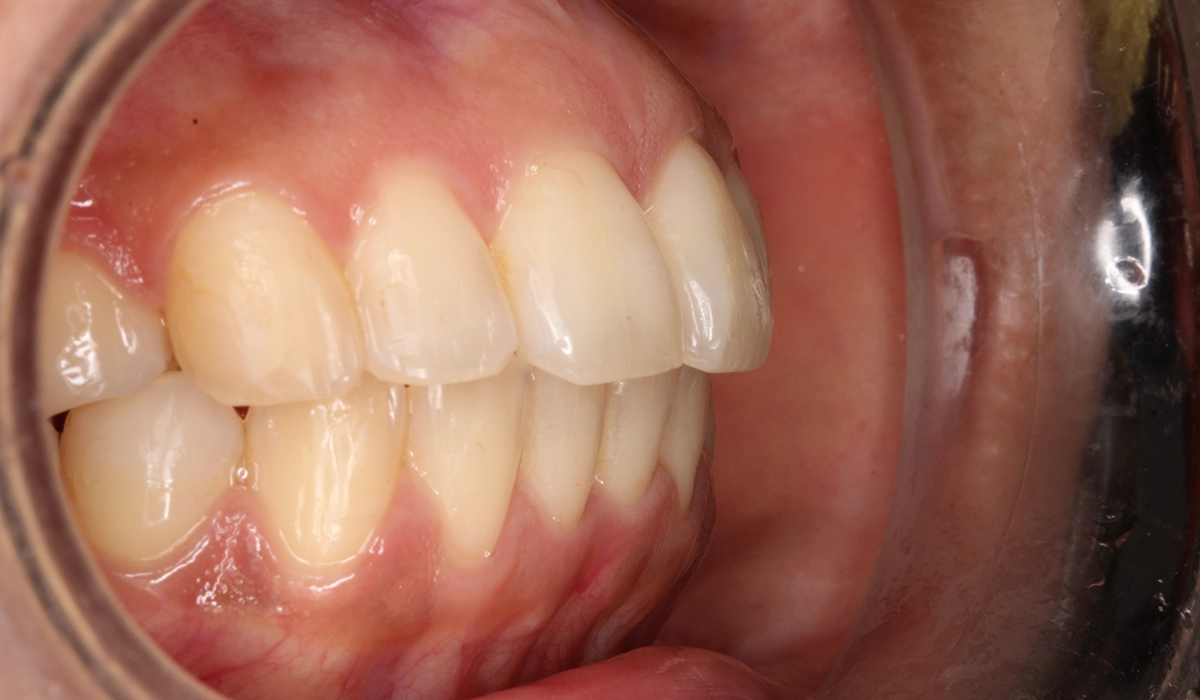

術前:右側

術後:右側